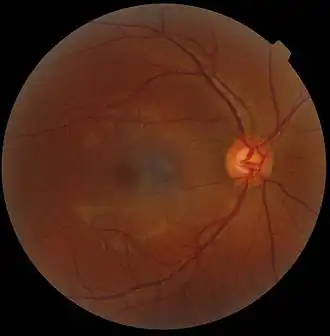

In microscopy, an artifact is an apparent structural detail that is caused by the processing of the specimen and is thus not a legitimate feature of the specimen. In light microscopy, artifacts may be produced by air bubbles trapped under the slide's cover slip.[1]